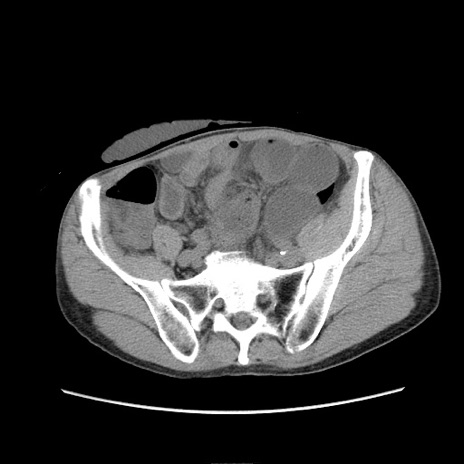

症例11(横断像)

【症例】 60歳代男性

【主訴】 下腹部痛

【現病歴】 本日夜中より下腹部痛の症状認め、受診。

【既往歴】 膀胱癌(膀胱全摘+尿管皮膚瘻術) 、胃癌術後

【身体所見】 BT 35.3℃、PR 58/min、BP 136/98mHg、腹部平坦、軟、腸蠕動音±、ストマ留置あり、左上腹部~正中部に圧痛あり、反跳痛なし。

【データ】WBC 5100、CRP0.01